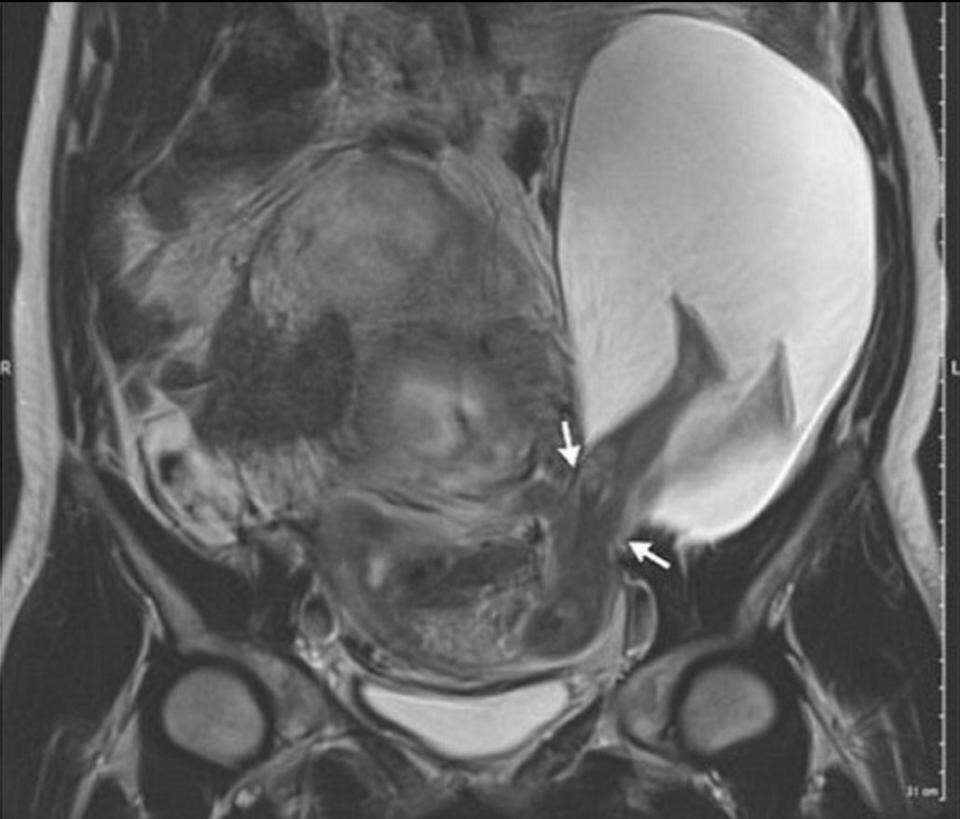

Na França, mãe gerou bebê com as pernas fora do útero